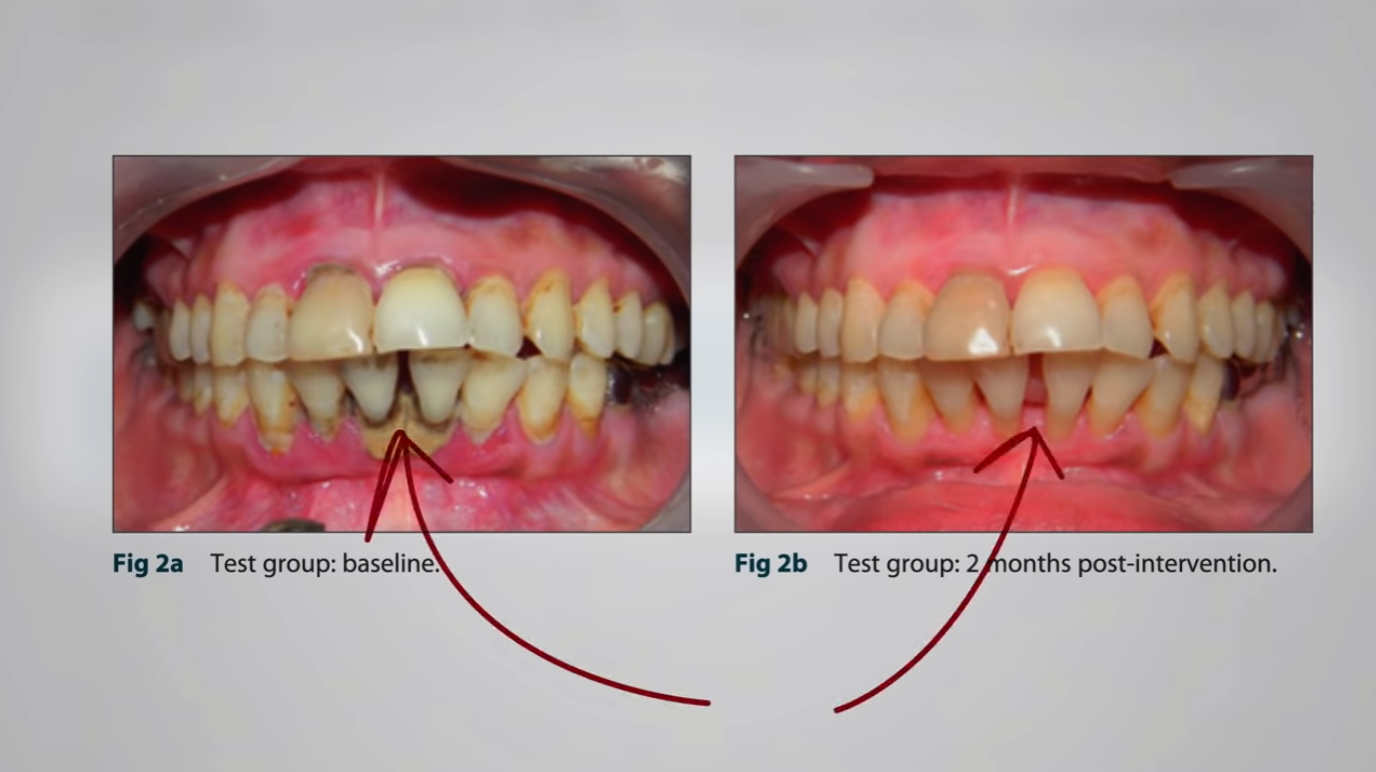

Another randomized, double-blind, placebo-controlled trial again treated subjects with a typical dental cleaning plus either one daily tomato’s worth of lycopene or a placebo for two months. Researchers found significant improvements in the lycopene group in plaque, gingivitis, and bleeding, though not probe pocket depth and clinical attachment. You can see the difference in how much better their gums looked as you can see below and at 5:59 in my video. The researchers concluded that “supplementation with lycopene seems to have augmented the healing sequence of inflamed gingival tissues,” but that was with a whole tomato’s worth a day. How about half a tomato’s worth or just three quarters of a teaspoon of tomato paste’s worth of lycopene a day? Neither worked. There was no difference. It looks like you have to go the whole tomato.